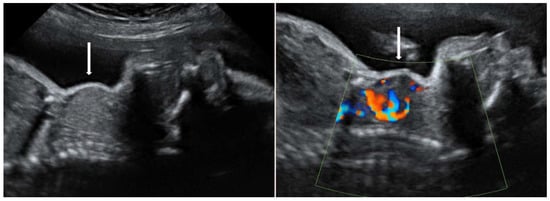

3.1. Graves’ Disease—TRAb Antibodies

- Huel, C.; Guibourdenche, J.; Vuillard, E.; Ouahba, J.; Piketty, M.; Oury, J.F.; Luton, D. Use of ultrasound to distinguish between fetal hyperthyroidism and hypothyroidism on discovery of a goiter. Ultrasound Obstet. Gynecol. 2009, 33, 412–420. [Google Scholar] [CrossRef] [PubMed]

- Panaitescu, A.; Nicolaides, K. Fetal Goitre in Maternal Graves’ Disease. Acta Endocrinol. (Buchar.) 2018, 14, 85–89. [Google Scholar] [CrossRef]

- Kobayashi, M.; Yagasaki, H.; Saito, T.; Nemoto, A.; Naito, A.; Sugita, K. Fetal goitrous hypothyroidism treated by intra-amniotic levothyroxine administration: Case report and review of the literature. J. Pediatr. Endocrinol. Metab. 2017, 30, 1001–1005. [Google Scholar] [CrossRef]